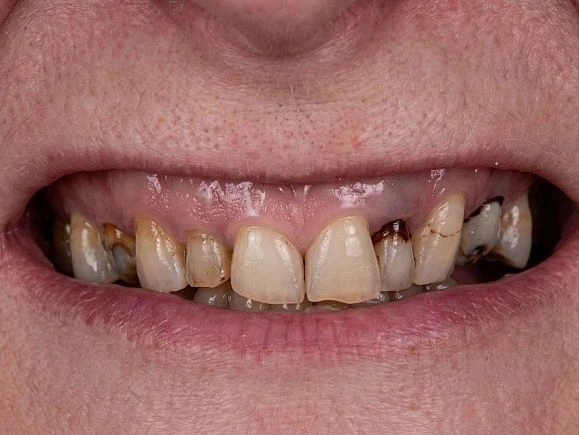

- Врожденные аномалии зубных рядов, попадающих в видимую зону при разговоре и улыбке

- Наличие широких межзубных промежутков

- Неровности зубного ряда

- Пятна на эмали, которые нет возможности убрать с помощью процедуры профессиональной чистки

- Трещины, сколы эмали

- Чтобы восстановить эстетику передних зубов, лучшим выбором будут виниры или люминиры;